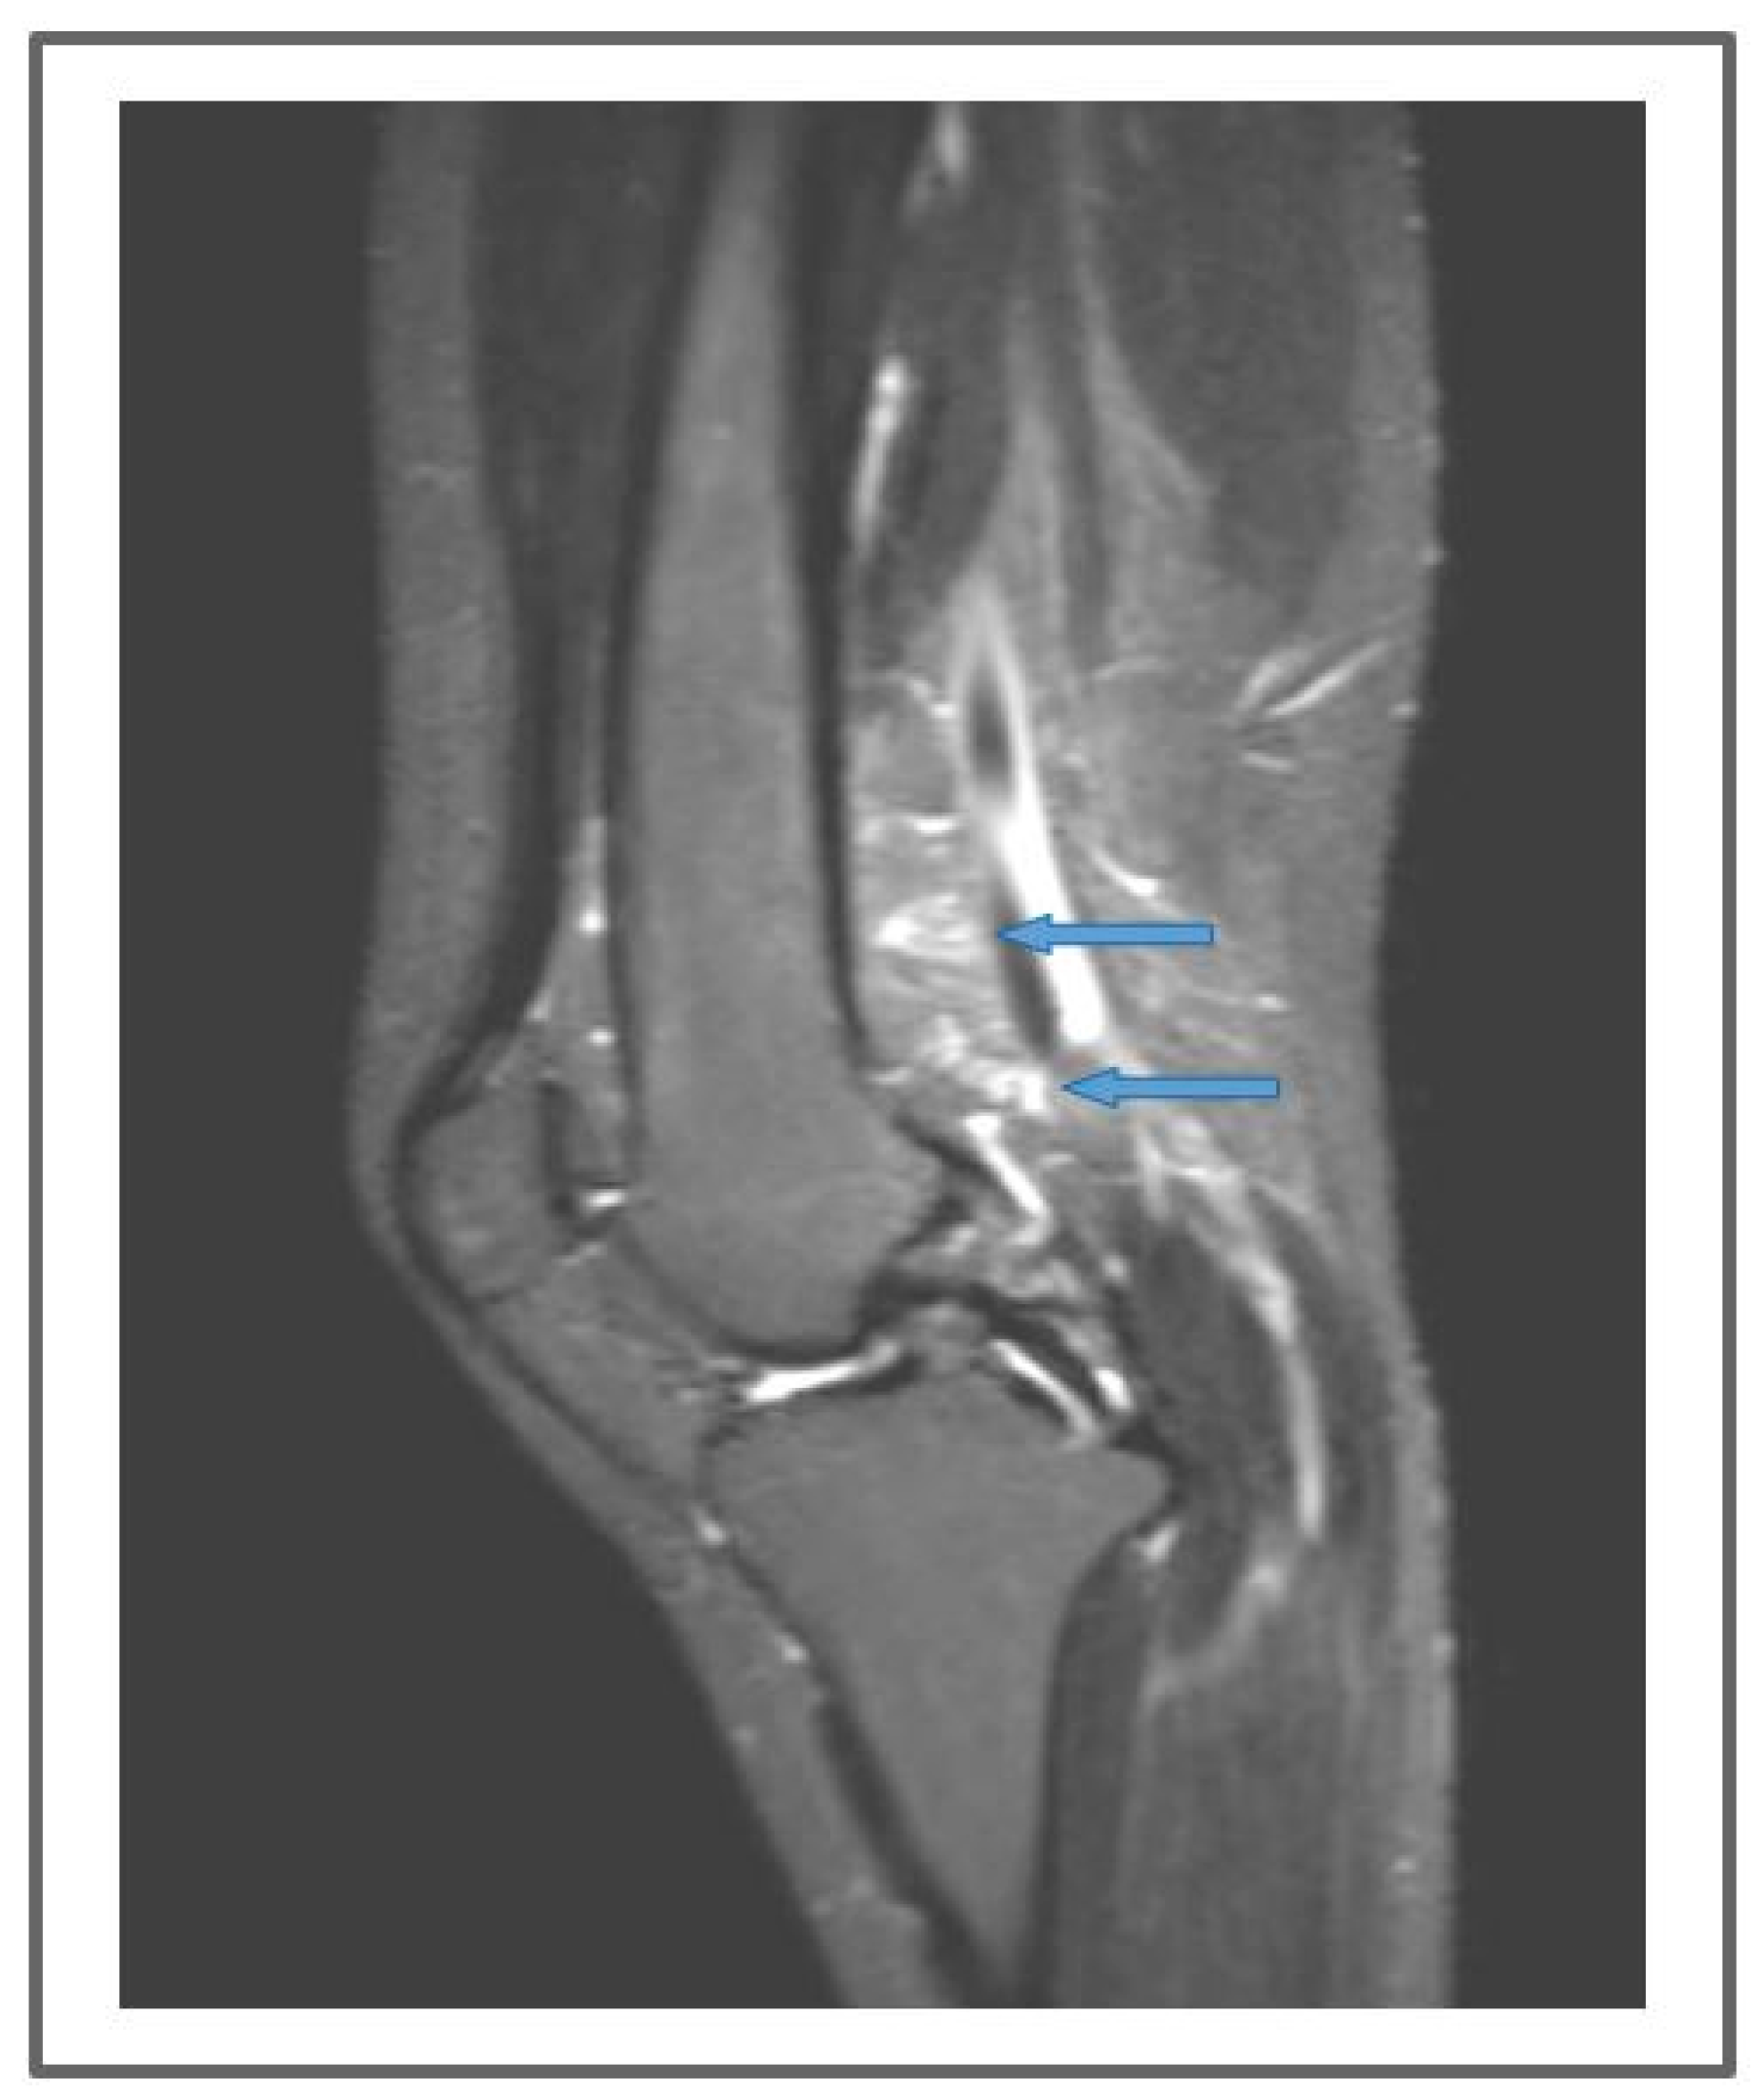

Figure 10.

Preoperative non-contrast MR lymphography (based on high-resolution heavily T2-weighted coronal sequences (turbo spin echo with repetition time 2870 ms, echo time 797 ms, field of view 380 × 380 mm, matrix 358 × 384, slice thickness 1 mm) (a) and follow-up non-contrast MR lymphography (b) 1-year post-venolymphatic-anastomosis. Marked edema involving the lower third of the leg, the ankle, and the dorsum of the foot (blue arrows) is visible in (a), while follow-up imaging (b) shows a reduction of the edema (blue arrows), but without evidence of any new lymphatic vessels.